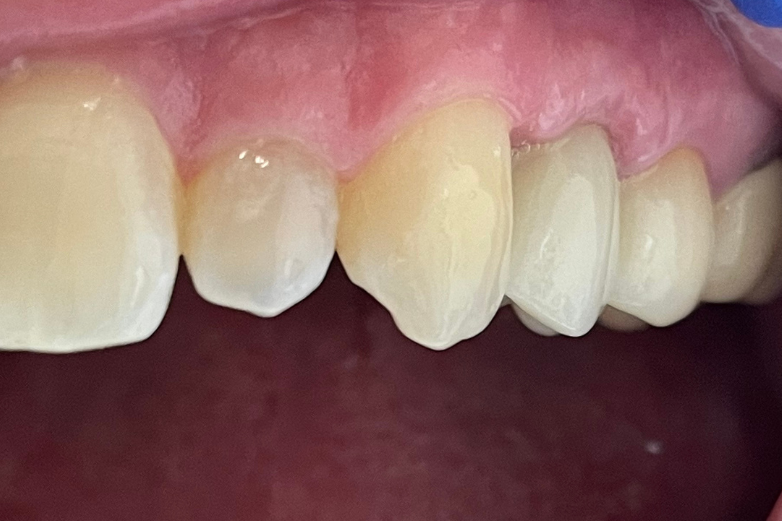

CHECK OUT THIS AWESOME RESULTS

(use cursor to move arrows left and right to see before and after images)

Single tooth dental implant treatment